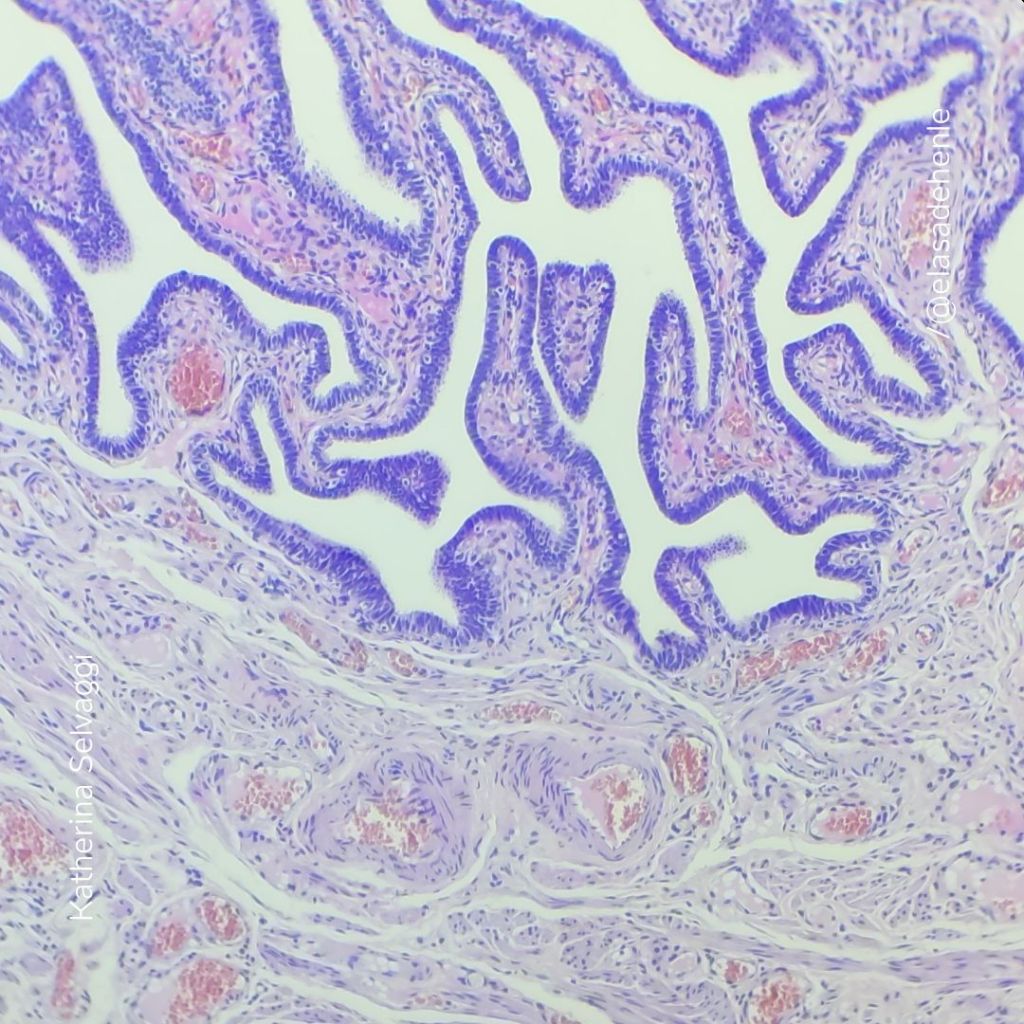

Hematoxilina y eosina

Trompa de Falopio.

COMECA

Hematoxilina y eosina

Trompa de Falopio

COMECA

Hematoxilina y eosina

Trompa de Falopio

COMECA